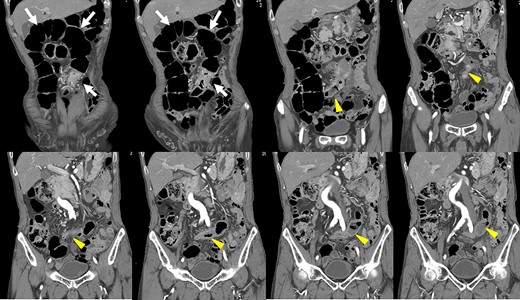

Preoperative computed tomography (CT) revealed a tumor in the sigmoid colon accompanied by some regional lymph node swelling (Fig. 1). It also showed that the IVC ascended vertically along the left side of the abdominal aorta. After connecting with the left renal veins, the left-sided IVC crossed the abdominal aorta anteriorly to join the normal prehepatic segment of the IVC (Figs 2 and 3). Coronal CT showed that the descending colon misplaced at the abdominal midline and the sigmoid colon in the right upper abdomen (Fig. 4). The preoperative diagnosis was thus sigmoid colon cancer with left-sided IVC and PDM.

After coronal reformation, the CT images show that the descending colon was at the midline of the abdomen (arrowheads), and the sigmoid colon was in the right upper abdomen (arrows).

PDM is a developmental anomaly characterized by failure of the descending mesocolon mesentery to fuse with the posterolateral parietal peritoneum [2]. The non-fused mesentery is then responsible for considerable variations in the position of the descending mesocolon. In our case, the descending colon was at the abdominal midline, and the sigmoid colon was in the right upper abdomen. Coronal reformatted images obtained by multidetector CT (MDCT) proved useful for an accurate preoperative diagnosis of the malpositioned descending colon. It is widely accepted that MDCT is an effective technique for staging colon cancer preoperatively [10]. MDCT also allowed us to generate multiplanar coronal images, which depicted the location of the colon as it would appear during the surgery. Moreover, MDCT angiography can be used to evaluate the running direction of the vessels. Because it has been reported that the left colon and sigmoid colon arteries and the superior rectal artery often branch radially from the inferior mesenteric artery, and that a marginal vessel may run abnormally due to the unusual mesenteric adhesion [5], accurate evaluation of the arteries is important for safe lymph node dissection.